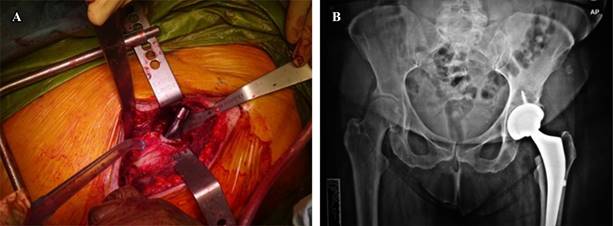

A more severe complication is the broaching-related perforation of the femoral cortex as a result of improper broach location (Figure 4).

Figure 4: Lateral femoral cortex perforation. X-ray taken to verify a resistance change during femoral canal preparation. A) Lateral cortex perforation fracture not compromising the stem stability. B) postoperative anteroposterior (AP) pelvis X-ray

One must be aware of the femur’s situation because a posterior perforation translates into a perforation of the lateral femoral cortex (extreme varus) when the femur is 90° or more externally rotated during preparation. Superior soft tissues can occasionally direct the broach in this direction.